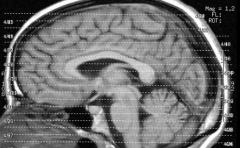

El coeficiente de inteligencia de una persona está relacionado con el grosor de su corteza cerebral, según una investigación en la que participaron varios centros de España, Reino Unido, EEUU y Canadá.ver más

Este lunes comenzó en Punta del Este la Cuarta Escuela de Educación, Ciencias Cognitivas y Neurociencias para promover investigaciones cientÃficas vinculadas (entre otras temáticas) a la actividad cerebral del adolescente. En diálogo con El Espectador, Juan Valle Lisboa, investigador e integrante del Centro de Investigación Básica en PsicologÃa, informó sobre los últimos preparativos para la apertura de la nueva escuela.ver más